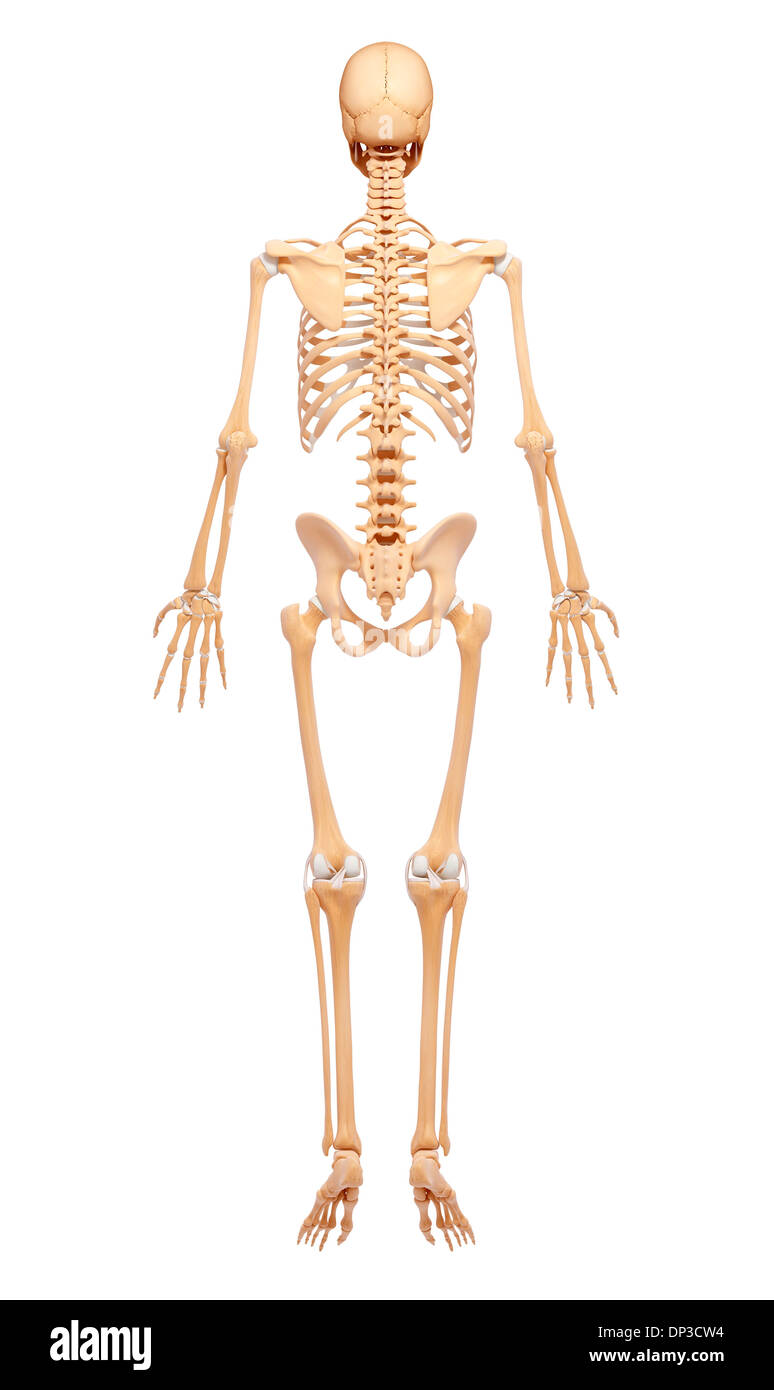

Human Skeleton, artwork Banque D'Imageshttps://www.alamyimages.fr/image-license-details/?v=1https://www.alamyimages.fr/human-skeleton-artwork-image65229504.html

Human Skeleton, artwork Banque D'Imageshttps://www.alamyimages.fr/image-license-details/?v=1https://www.alamyimages.fr/human-skeleton-artwork-image65229504.htmlRFDP3CW4–Human Skeleton, artwork